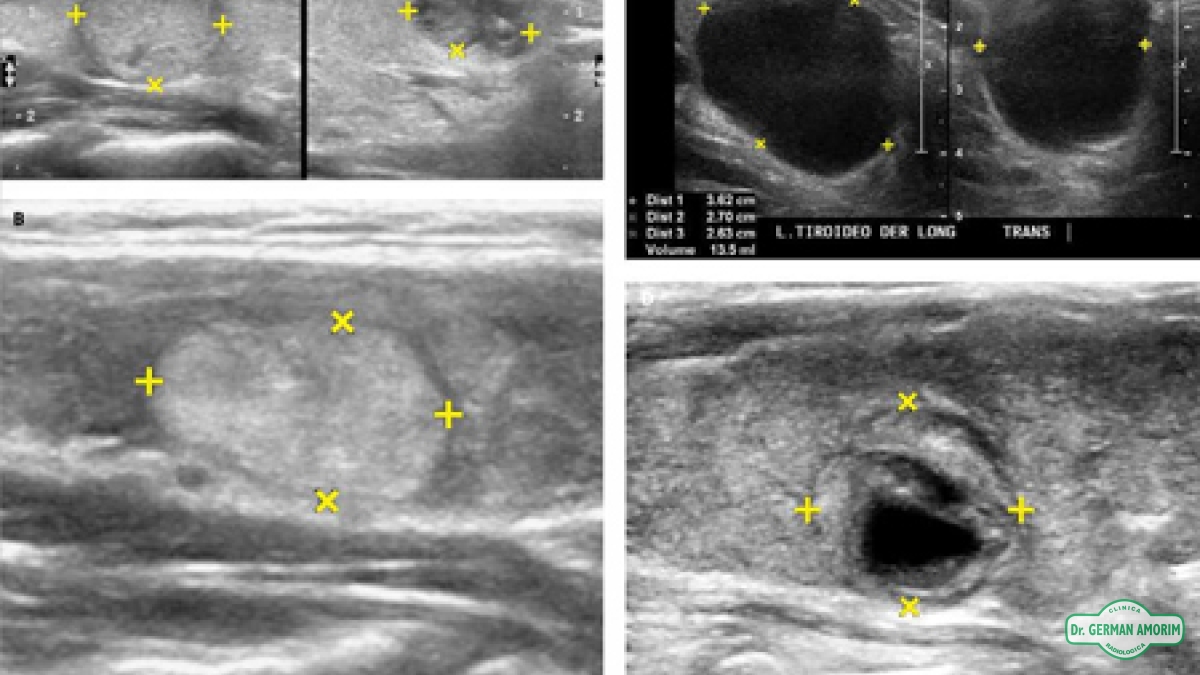

Las imágenes por ultrasonido es un examen médico no invasivo que ayuda a los médicos a diagnosticar y tratar condiciones médicas. El ultrasonido de tiroides produce imágenes de la glándula tiroides y estructuras adyacentes en el cuello. La glándula tiroides se ubica en la parte delantera del cuello, justo por encima del hueso de la clavícula, y tiene forma de mariposa, con un lóbulo a cada lado del cuello conectados por una banda estrecha de tejido. Es una de las nueve glándulas endocrinas ubicadas en el cuerpo que producen y envían hormonas al torrente sanguíneo.

La glándula tiroides produce la hormona tiroidea que ayuda a regular una variedad de funciones corporales, incluyendo la velocidad de latido de su corazón. Es muy común que en sus tiroides se desarrollen áreas irregulares o nódulos que pueden, o no, ser evidentes en la superficie de la piel. Aproximadamente entre el cinco al 10 porciento de los adultos tienen nódulos tiroideos, a veces palpables otras sólo localizados por ecografía.